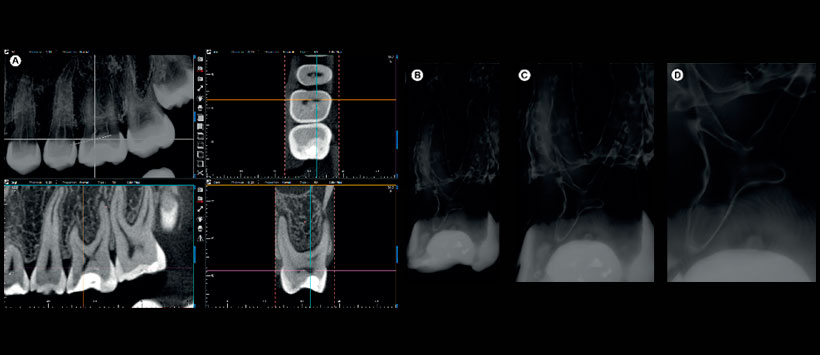

Figura 5: (A) Otro filtro transforma las imágenes CBCT en imágenes en modo transparente, como se muestra en el diente # 26; (B-D) Los detalles específicos de la cámara coronal, así como el volumen y las estructuras adyacentes se visualizan claramente.

Figura 6: (A-B) Las imágenes de e-Vol DX CBCT muestran la forma y la posición del foramen apical del diente # 35.